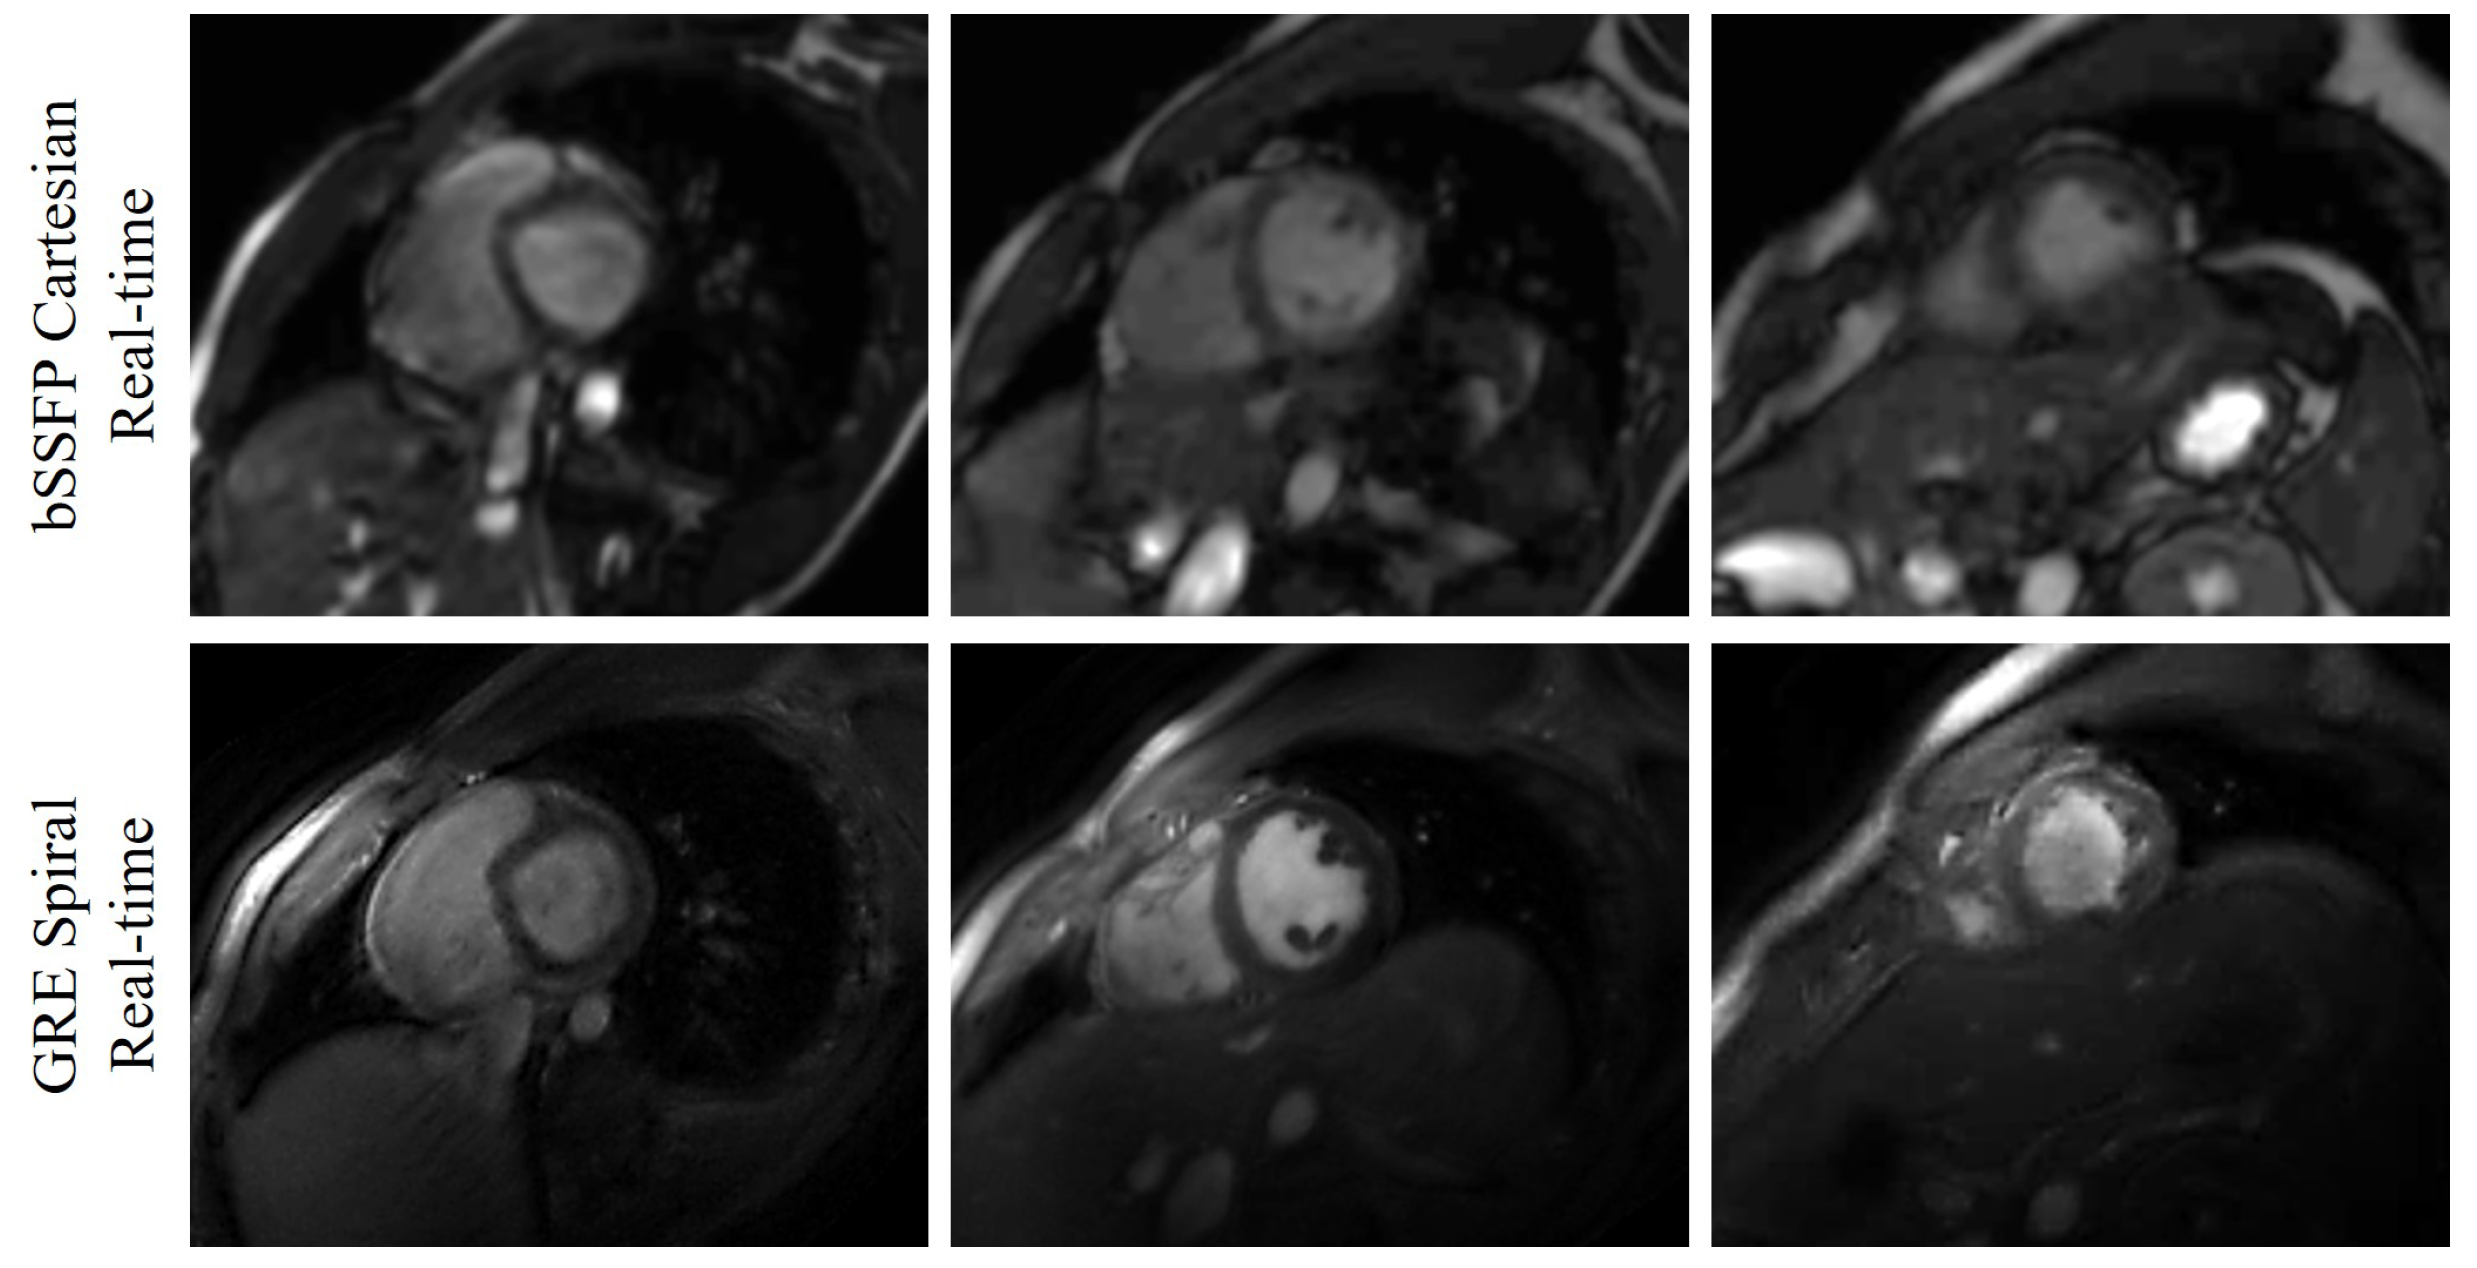

The output of each image has two channels, which correspond to the real and imaginary parts of the MR image. For the convolutional layers which have activation functions, we use Leaky ReLU with slope 0.2. Thirty-seven slices from five subjects were reconstructed in this work. Among the five subjects, we collected the basal slices for two subjects. The deep kernel method is also able to reconstruct the basal slices. The reconstructions of eight slices from Subject #2 were shown in Figure 2. We have also shown the comparison between the bSSFP Cartesian real-time images with acceleration factor 5 and the GRE spiral real-time images reconstructed using the deep kernel method in Figure 3.

Figure 3.

Comparison between the bSSFP Cartesian real-time images with acceleration factor 5 and the GRE spiral real-time images reconstructed using the deep kernel method. The three slices (one basal slice, one mid slice, and one apex slice) are from Subject #3. The first row shows the bSSFP Cartesian real-time images, and the second row is the GRE spiral real-time images.